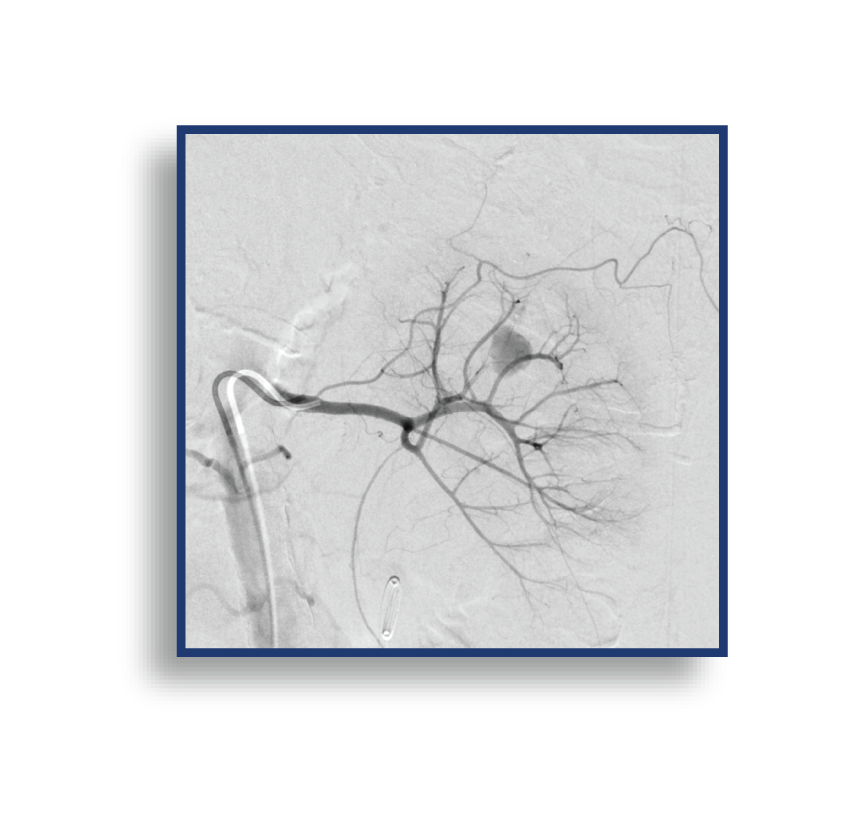

The LAVA Liquid Embolic System (LES) is The First and Only Liquid Embolic Approved for Peripheral Vasculature Hemorrhage.

LAVA provides the confidence to quickly stop bleeds results in controlled target vessel occlusion.

LAVA is available in a 2 mL vial and a 6 mL vial; both vials have an 18 or 34 viscosity option. These pre-mixed vials allow for both a proximal target embolization and a distal target embolization, providing options to reach the bleed. The 2 mL LAVA LES comes with two (2) 1 mL delivery syringes and the 6 mL LAVA LES offers six (6) 1 mL delivery syringes, enabling you multi-zone embolization options from 1 pre-mixed vial. An optional Mixing Kit is available to expedite the shaking of the vial, which suspends the radiopaque particles. The volume of the particles in LAVA has been designed to reduce flash for clear imaging.